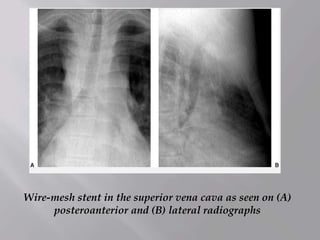

Wire-mesh stent in the superior vena cava as seen on (A)

posteroanterior and (B) lateral radiographs